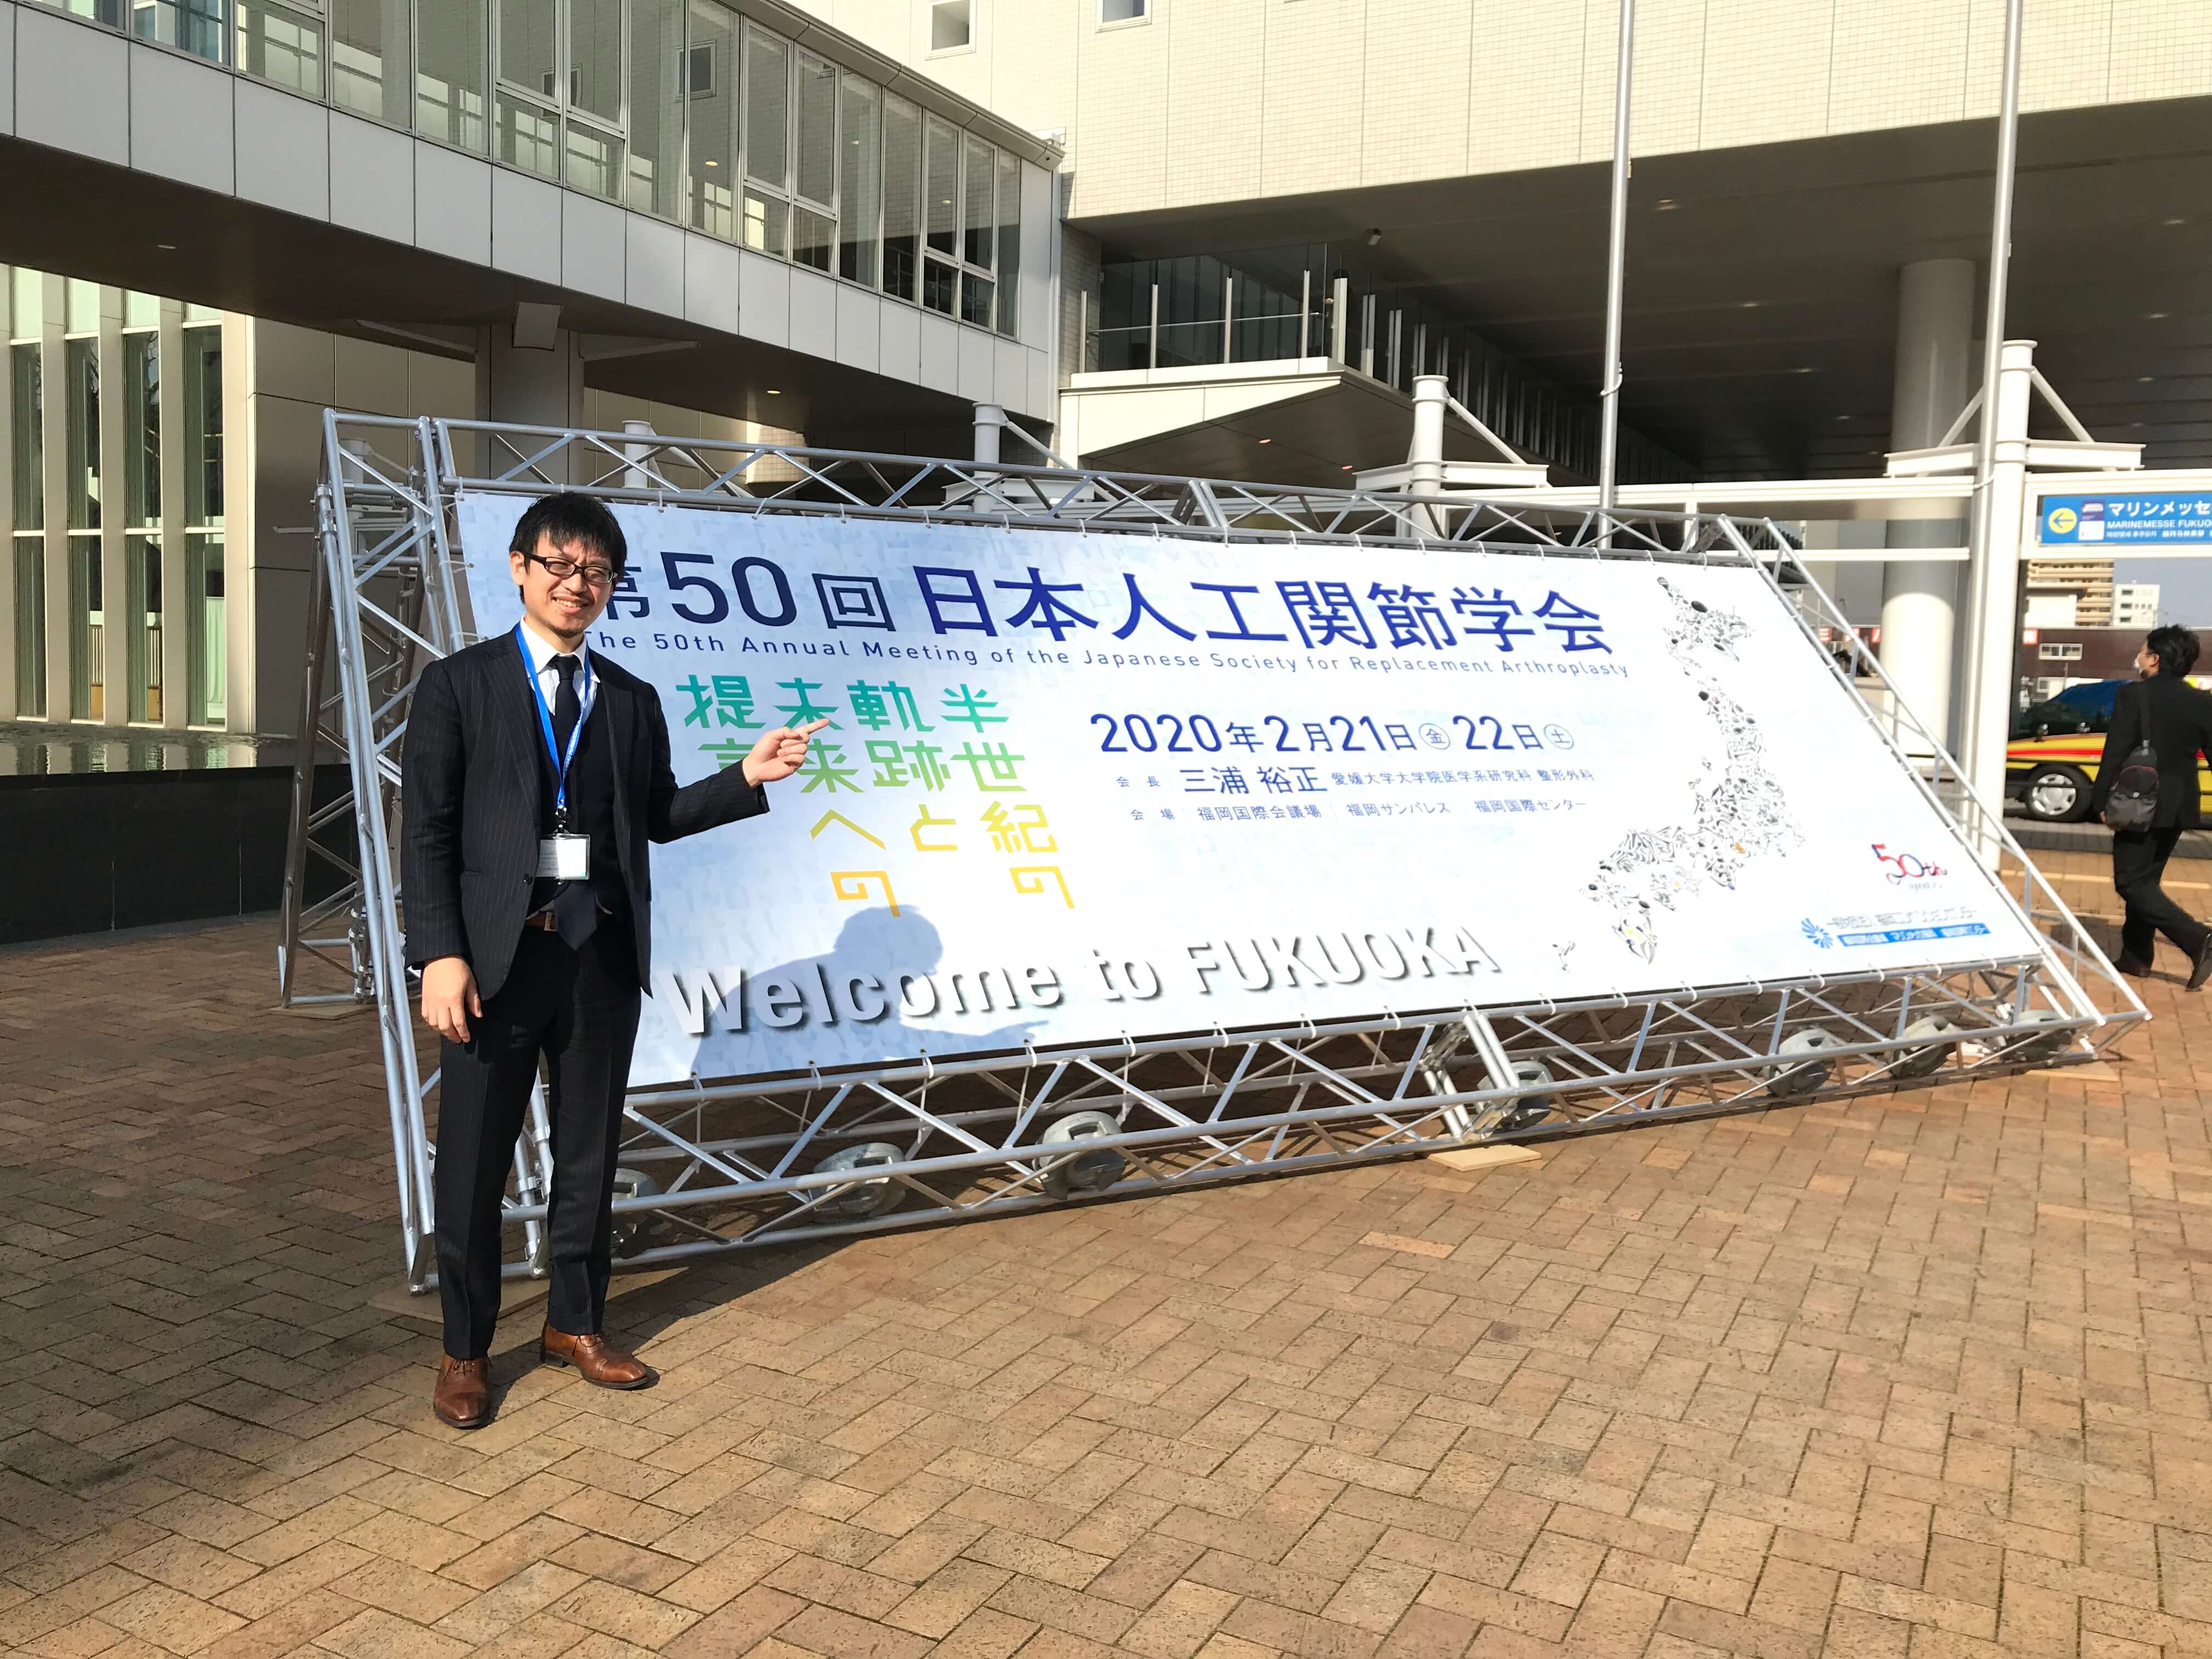

世田谷人工関節・脊椎クリニックの院長の塗山正宏です。

世田谷人工関節・脊椎クリニックの院長の塗山正宏でした。

世田谷人工関節・脊椎クリニック

整形外科・放射線診断科

股関節・膝関節・骨粗鬆症・脊椎・再生医療